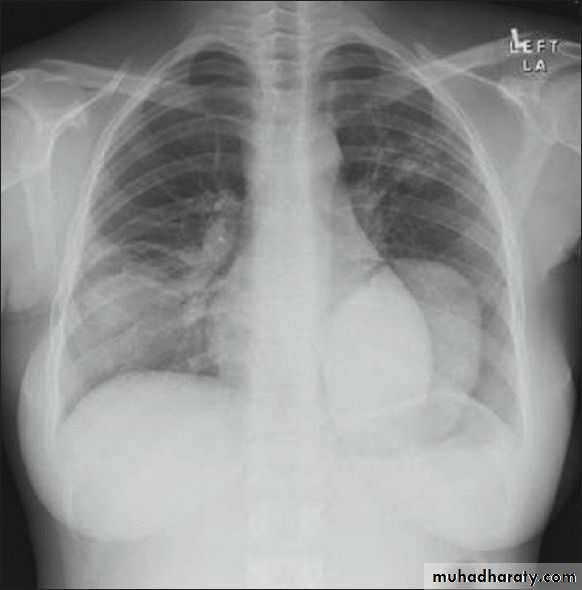

Abdominal surgery before 2 days

Fall from the 2nd floor